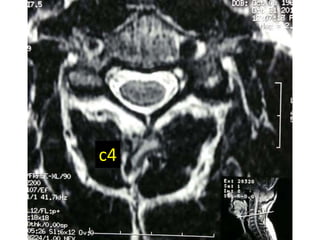

c4

C3C4

C4C5